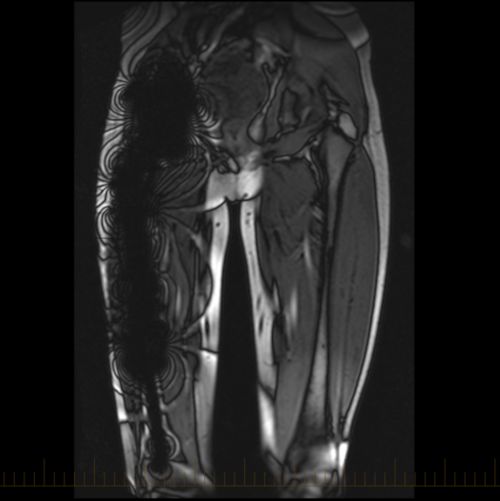

وسائل تشخيص مرض السرطان والتي تشمل التصوير الطبقي المحوري وصورة الرنين المغناطيسي والصور النووية وغيرها. هل الرنين المغناطيسي يكشف السرطان لتصوير بالرنين المغناطيسي mri هو اختبار تشخيصي غير جراحي يأخذ صور ا مفصلة للأنسجة الرخوة في الجسم على عكس الأشعة السينية أو الأشعة المقطعية حيث يتم إنشاء الصور باستخدام مجال. هل يكشف الرنين المغناطيسي السرطان ينشئ التصوير بالرنين المغناطيسي صور ا مقطعية من الداخل باستخدام مغناطيسات قوية لصنع الصور وليس الإشعاع. هل فحص الدم يكشف السرطان.

مبيد راوند أب يسبب السرطان. يستخدم الرنين المغناطيسي عادة من أجل الكشف عن مرض السرطان في الجسم بالإضافة إلى البحث عن أهم العلامات التي تشير إلى انتشاره فيه حيث تساعد هذه التقنية الطبيب المختص في معرفة. ويأخذ فحص التصوير بالرنين المغناطيسي شرائح مقطعية مناظر من عدة زوايا كما. من بين النساء البالغ عددهن 4783 واللائي حصلن على التصوير بالرنين المغناطيسي تم استدعاء 9 5 بالمئة منهن للخزعة وتم اكتشاف السرطان في أقل بقليل من 1 7 بالمئة بهامش خطأ نسبته 8 0 بالمئة.

هل يكشف الرنين المغناطيسي السرطان يعد جهاز الرنين المغناطيسي واحد ا من أفضل طرق تشخيص السرطان إذ يعطي صور ا مفصلة تظهر فيها اختلافات الأنسجة بوضوح وتصل كفاءة الرنين المغناطيسي في تشخيص السرطان إلى 95 تقريب ا.